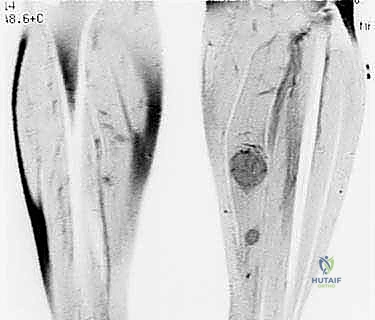

- الأشعة المقطعية (CT Scan): ضرورية لتقييم القشرة العظمية والتكلسات داخل الورم، وللبحث عن أي انتشار في الرئتين.

لضمان أخذ العينة من الجزء الأكثر تمثيلاً للورم وتجنب المناطق الميتة (Necrotic areas)، يستخدم الدكتور هطيف جهاز الأشعة المقطعية أو جهاز القوس المفلور (C-arm) لتوجيه الإبرة في الوقت الفعلي.

3. إدخال الإبرة واستخراج العينة

يقوم الدكتور بإجراء شق دقيق جداً (لا يتجاوز بضعة ملليمترات) في الجلد. يتم إدخال الإبرة المجوفة عبر مسار تم التخطيط له مسبقاً بعناية فائقة. يتم سحب عدة عينات أسطوانية من أماكن مختلفة داخل الورم لضمان دقة التشخيص.